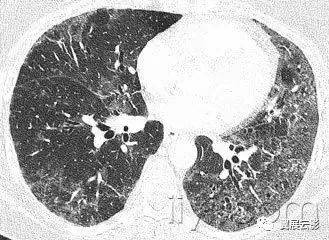

图示为多灶性的肺实变。

十九、肺实变:

病理学:肺实变是指渗出,或者其他疾病成分替代肺泡内气体,导致肺实变。

平片和CT:肺实变表现为肺实质密度的均匀一致性增高,导致肺血管和气道壁边缘不清。有时可见含气支气管征。只有在极少数的情况下,肺实变的密度变化有助于鉴别诊断,例如脂性肺炎是密度减低,胺碘酮中毒时密度增高。